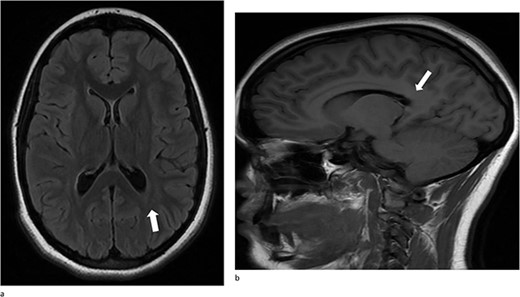

A 13-year-old female presented with an abrupt onset of a severe headache accompanied by two episodes of vomiting, left-sided jaw pain, nausea, and nasal congestion. She did not report any numbness, tingling, muscle weakness, or changes in vision. An initial non-contrast CT scan of the head revealed a left lateral intraventricular hemorrhage, (Fig. 1a). There were no intraparenchymal hemorrhages, midline shifts, or extra-axial fluid accumulations. MRI revealed a hemorrhagic lesion measuring 2.1 cm × 1.6 cm × 2.6 cm, involving the left atrium and the adjacent periventricular deep white matter (Fig. 1b). There was thickening of the choroid plexus, with no significant vasogenic edema or acute extra-axial fluid collection, and no signs of brain herniation.

(a)–(d) Demonstrates evidence of a hemorrhagic lesion involving the left atrium and adjacent periventricular deep white matter with a moderate amount of intraventricular hemorrhage within the left ventricle.